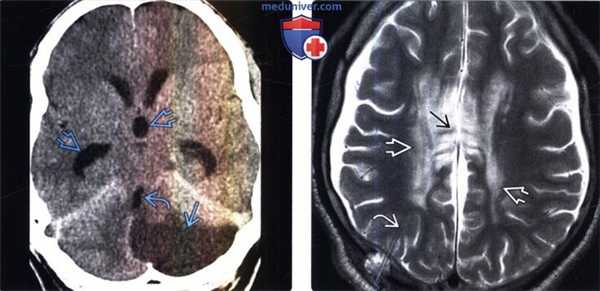

(Слева) КТ с контрастированием, аксиальный срез: определяется подострый инфаркт мозговой ткани в бассейне кровоснабжения левой задней нижней мозжечковой артерии, обусловливающий масс-эффект на IV желудочек и приводящий к обструктивной гидроцефалии.

(Справа) МРТ, Т2-ВИ, аксиальный срез: у пациента с импиджмент-синдромом мозолистого тела после шунтирования по поводу тяжелой ВЖОГ визуализируются шунт, субдуральные скопления жидкости с обеих сторон и гиперинтенсивные полосовидные участки в мозолистом теле с менее выраженными изменениями в перивентрикулярном БВ.

(Слева) МРТ, Т1-ВИ, сагиттальный срез: в верхней мозжечковой цистерне определяется крупная арахноидальная киста, оказывающая выраженный масс-эффект на пластинку четверохолмия и водопровод мозга. Отмечаются расширение III и боковых желудочков, истончение мозолистого тела.

(Справа) MPT, FLAIR, аксиальный срез: определяется массивное расширение III и боковых желудочков вследствие объемного образования ликворной интенсивности сигнала в III желудочке. Кроме того, отмечается пери вентрикулярный интерстициальный отек. При хирургическом вмешательстве была обнаружена и фенестрирована эпендимальная киста III желудочка.